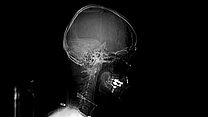

Bei dem Filmemacher Sobo Swobodnik wurde 2014 bei einer Routineuntersuchung ein Aneurysma im Gehirn entdeckt. Die Ärzte wollten keine Zeit verlieren und die Aussackung der Arterie so schnell wie möglich operativ behandeln. Doch zuerst einmal musste herausgefunden werden, wo genau die betroffene Arterie liegt und mit welcher Methode anschließend operiert werden kann. Sobo Swobodnik beschäftigt sich in seinem Dokumentarfilm mit seiner eigenen Diagnose, thematisiert, was sie in ihm ausgelöst hat und begleitet die zwei langen Monate, bis er endlich operiert werden kann, mit der Kamera. Anhand seiner eigenen Notizen aus dieser Phase, versucht er sich seiner eigenen Extremsituation wieder zu nähern.